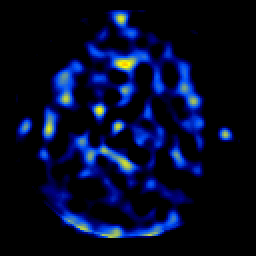

SPECT TL Study #6 -- Slice #27

[Home][Help][Clinical][Tour 1][Tour 2][Tour 3] Slice 27